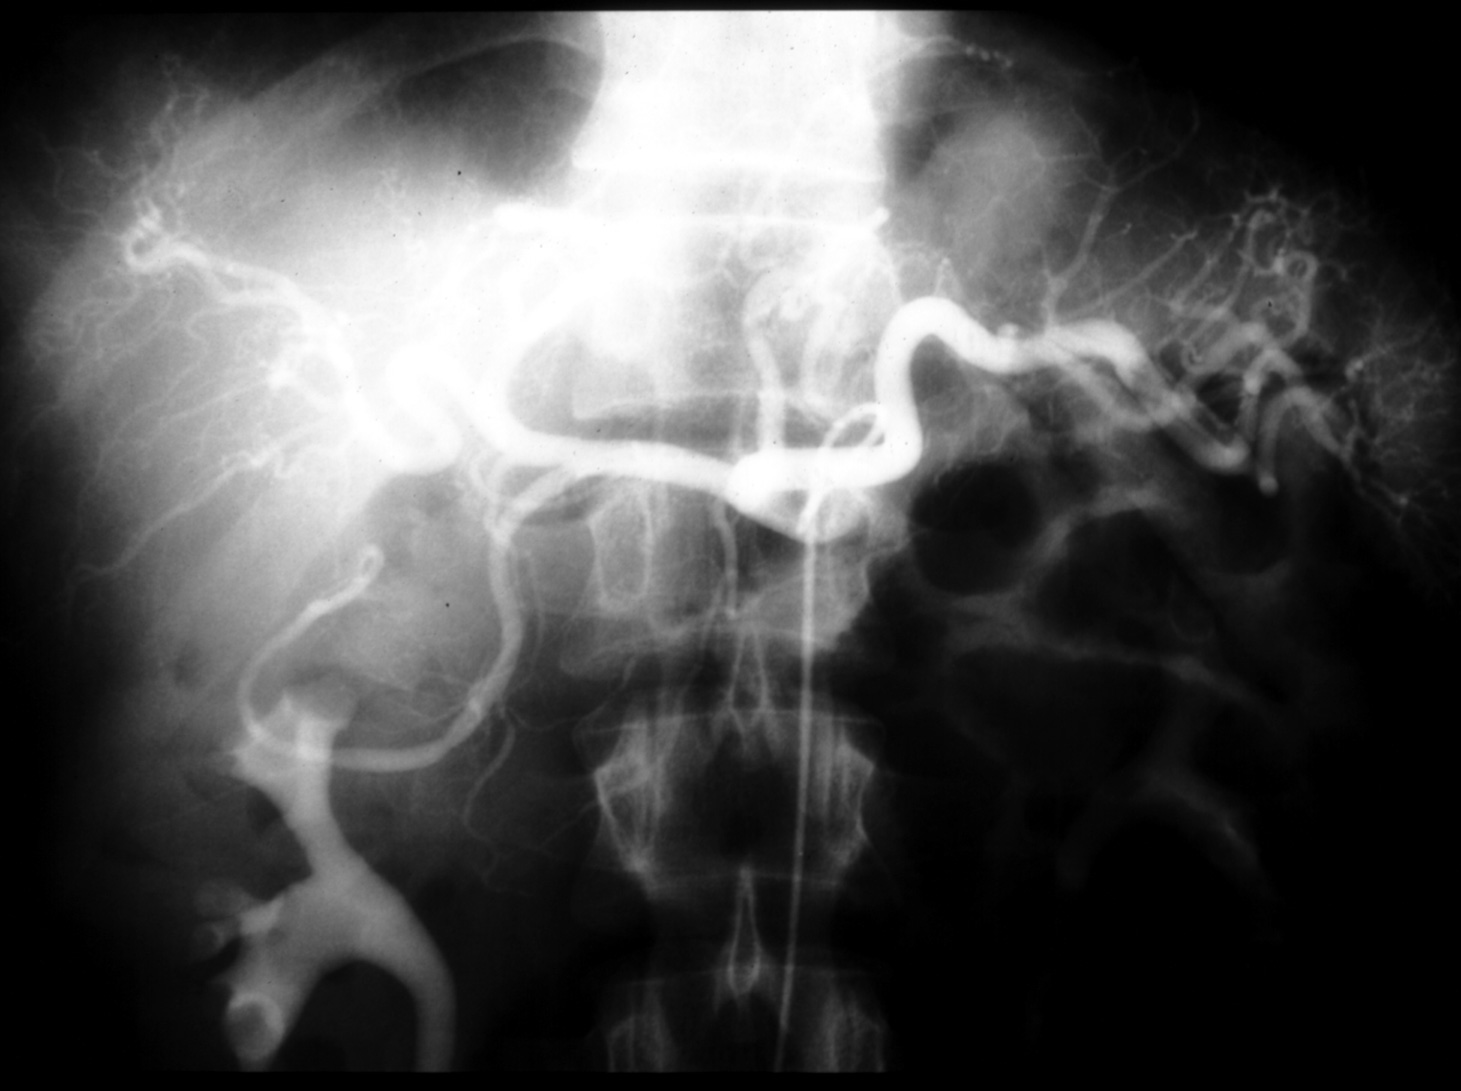

MS I ??? - Celiac Arteriogram (Arterial Phase)

Identify:  main hepatic, splenic left gastric, hepatic proper, gastroduodenal, right and left hapatic arteries